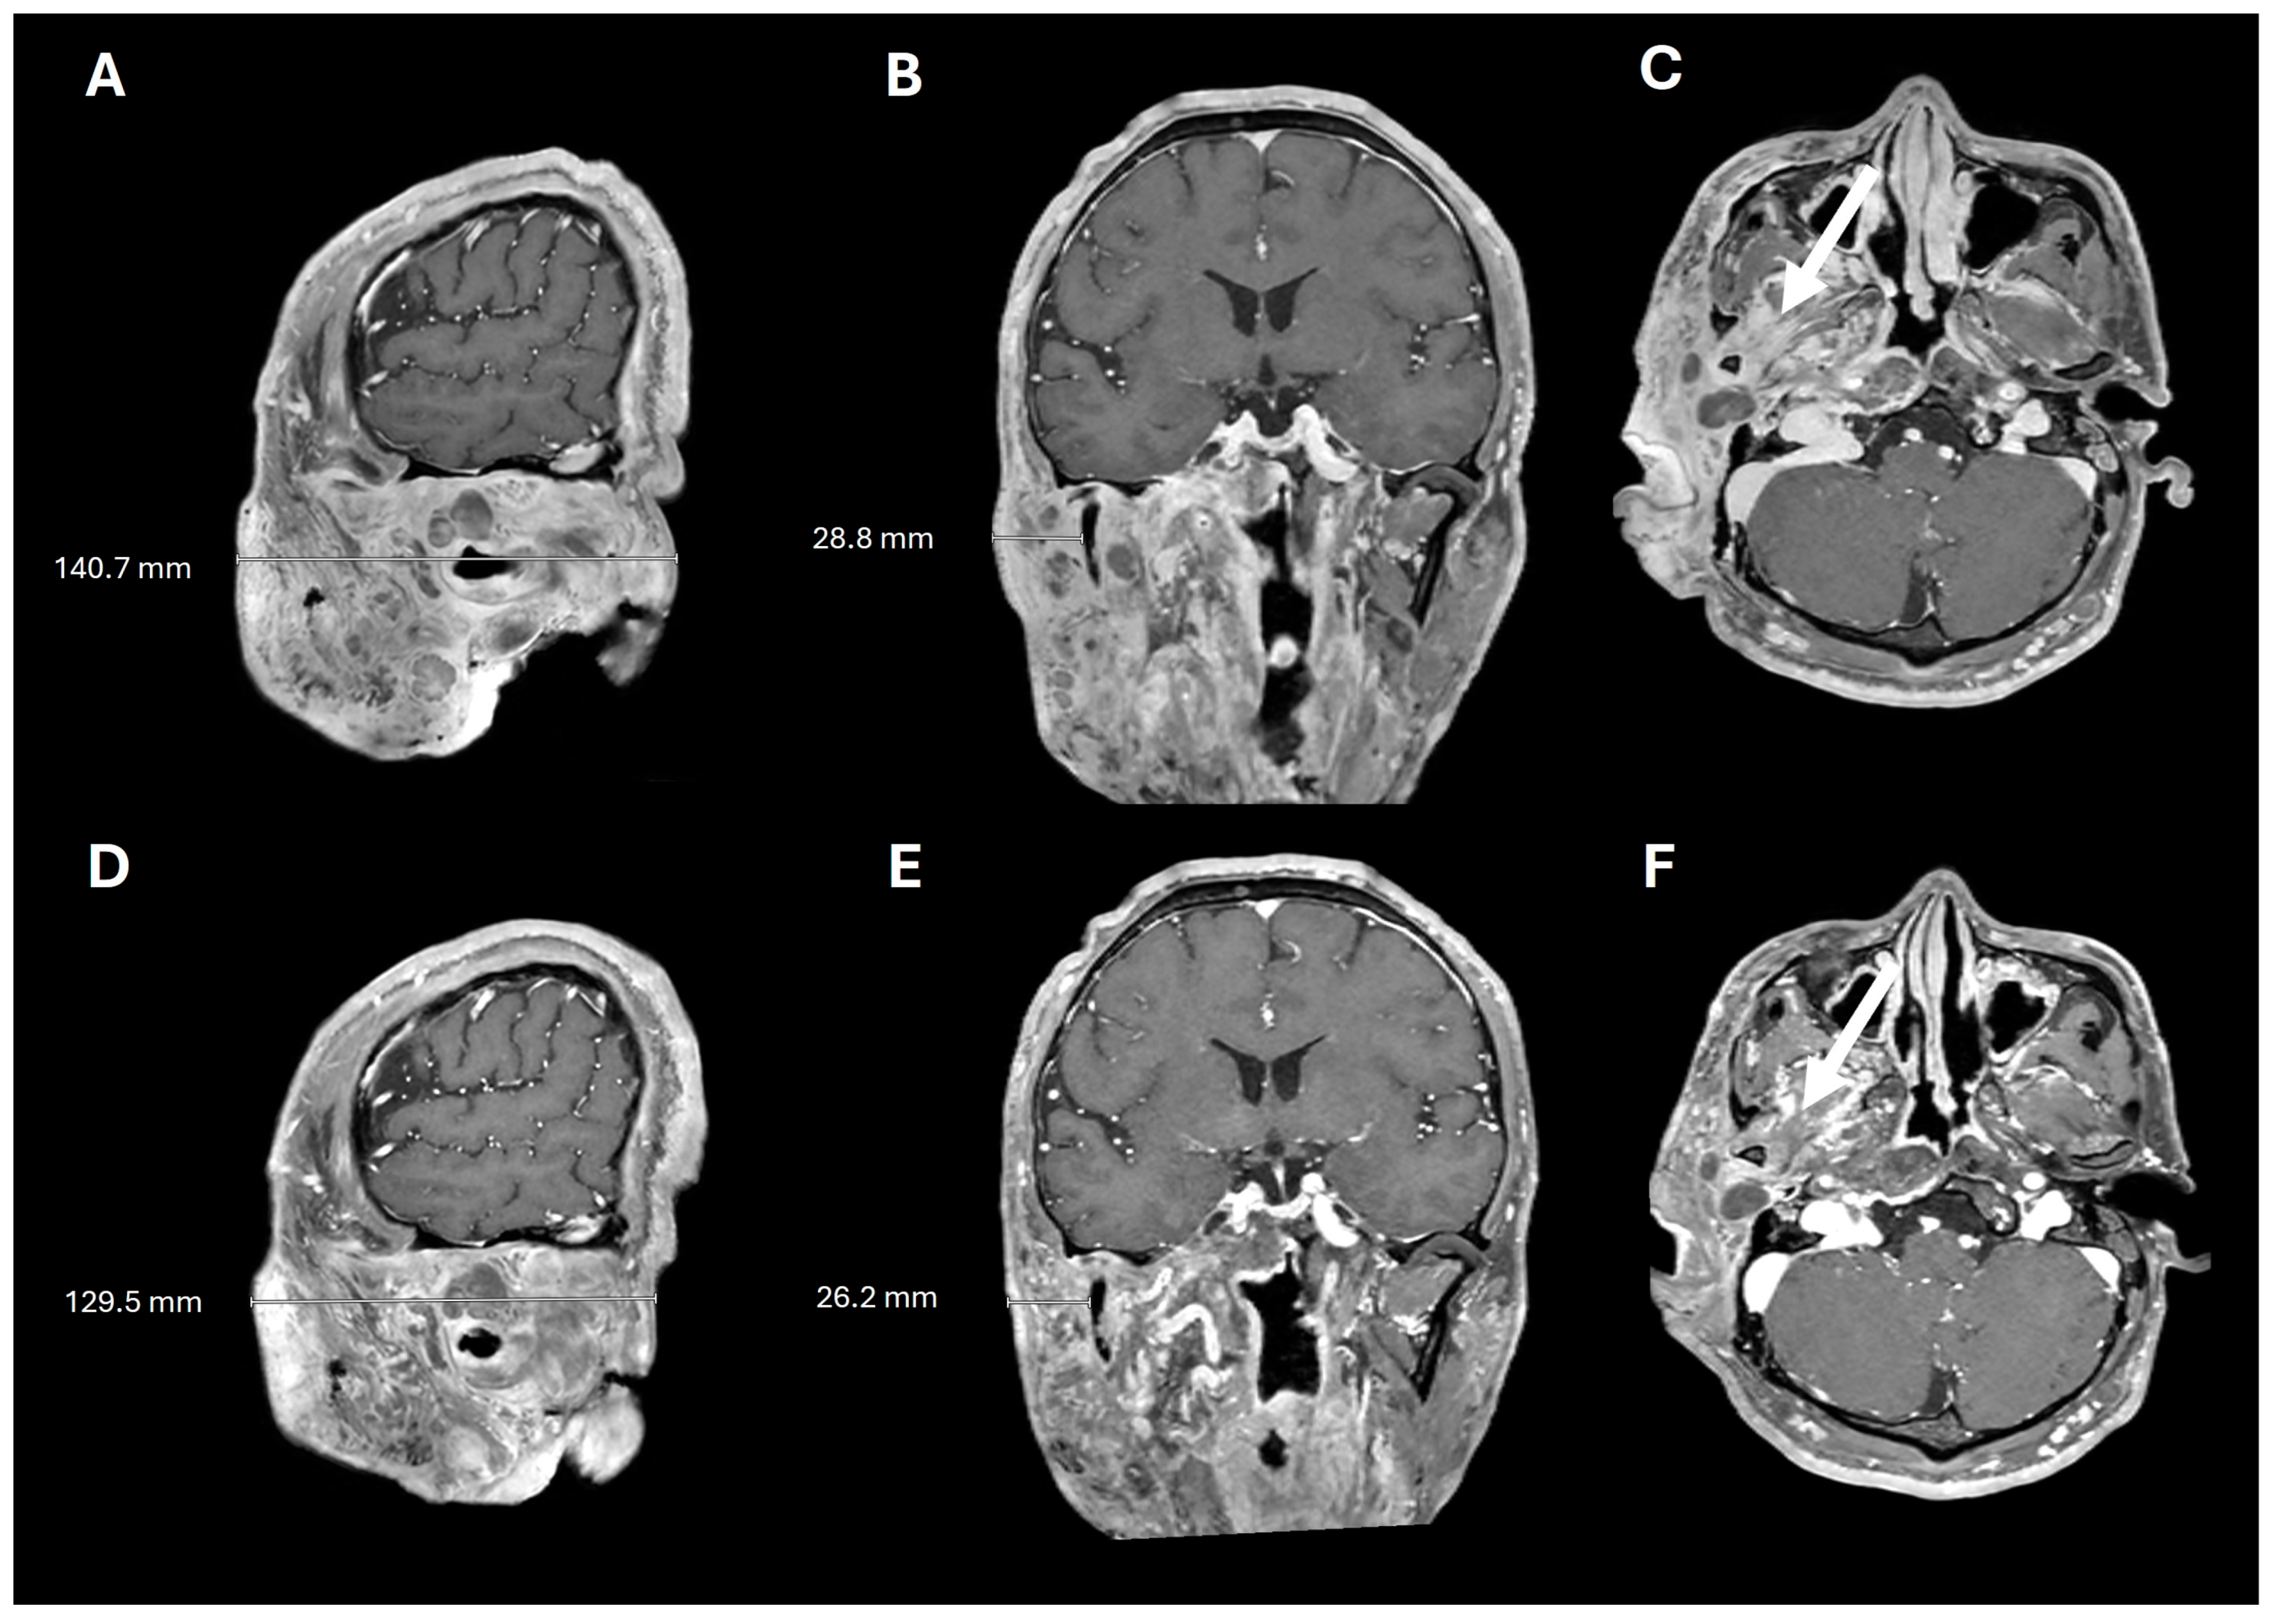

2. Case Presentation